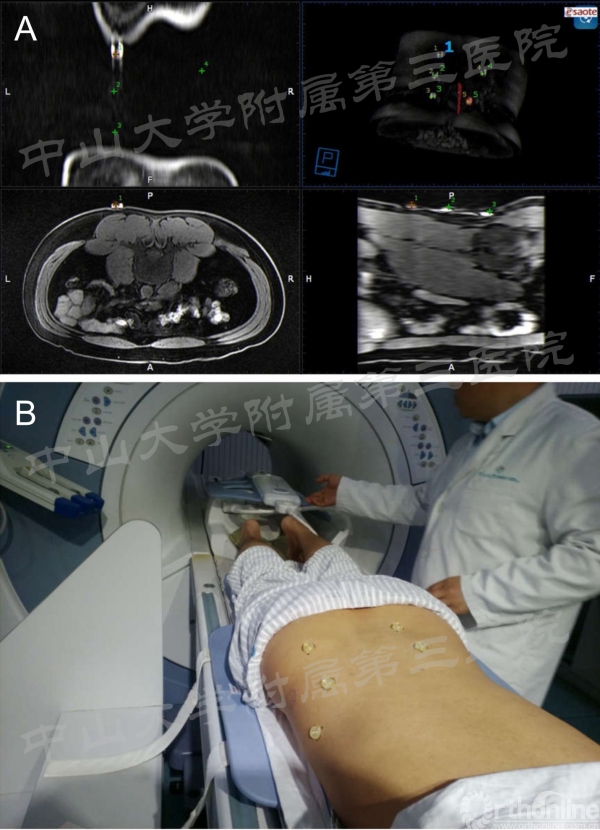

图2:A:术前提前下载MR图像,并通过体表定位标注注册;B:患者采用俯卧位进行检查,与手术中体位一致。

将已获得的磁共振图像导入esaote影像融合系统The MyLab Twice(Esaote, Italy)。此系统拥有超声探头、磁定位仪、vtrax针尾导航定位器。术中超声探头所扫描到的图像,能转化为磁共振上对应的层面,并能通过外定标配准的方法,将超声图像与磁共振图像融合。